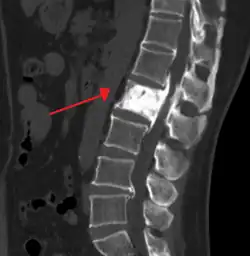

| "This 92 year-old male patient presented for assessment of sudden inability to move half his body. An incidental finding was marked thickening of the calvarium. The diploic space is widened and there are ill-defined sclerotic and lucent areas throughout. The cortex is thickened and irregular. The findings probably correspond to the 'cotton wool spots' seen on plain films in the later stages of Paget's disease." | |